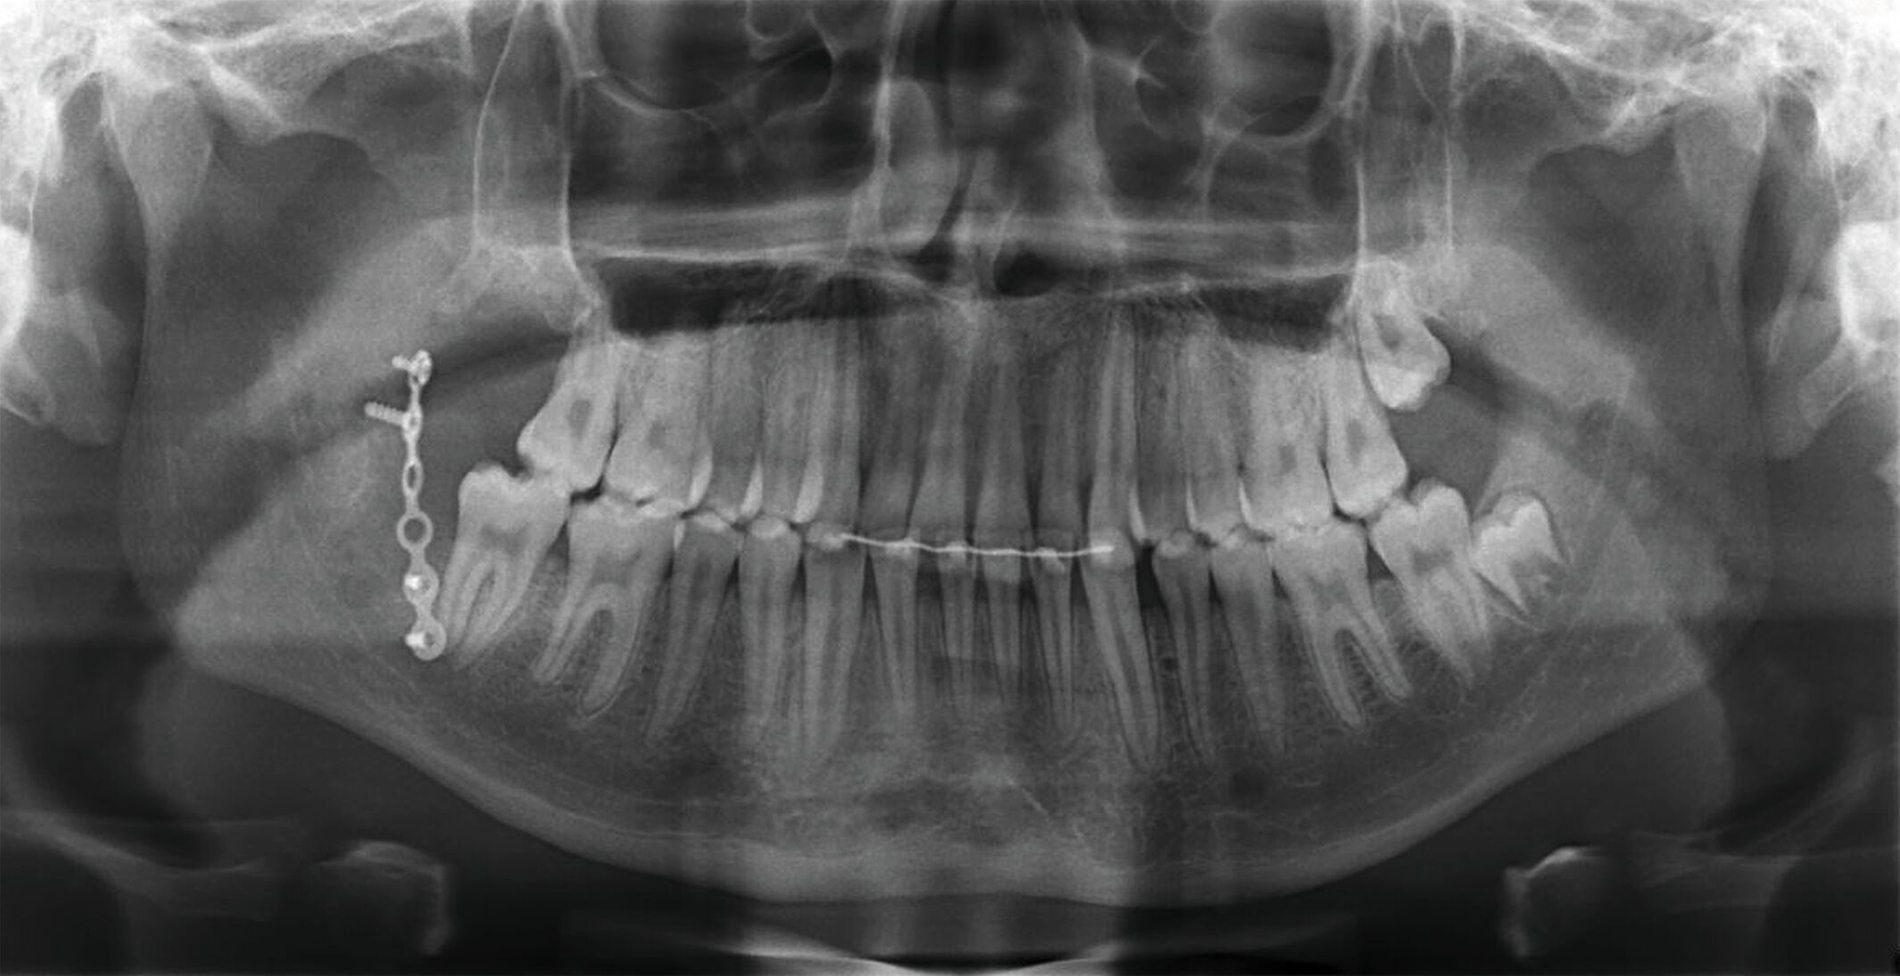

Nach ausführlicher Besprechung der Diagnose und der Therapieoptionen erfolgte am nächsten Tag die Reposition und Osteosynthese in Intubationsnarkose. Dabei konnte die Fraktur reponiert und mittels 6-Loch-Platte nach Champy stabilisiert werden (Abbildung 3). Der Patient konnte bei regelhafter postoperativer radiologischer Kontrolle am dritten postoperativen Tag in die ambulante Nachsorge entlassen werden.